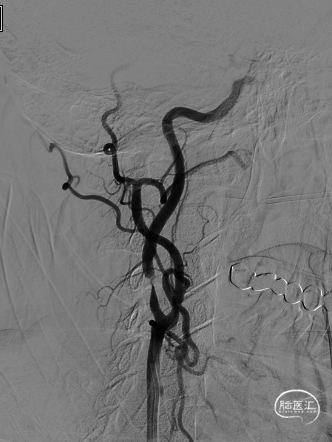

长SIM与6F导引导管同轴,泥鳅导丝引导下将6F导引导管送至颈总动脉远端(左图),保护伞到位(右图)。

4.0*30mm通桥白驹®球囊以6atm扩张(左图箭头),扩张完毕后多角度造影显示狭窄交前明显改善(中图箭头处),扩张完毕后支架置入(右图箭头处)。